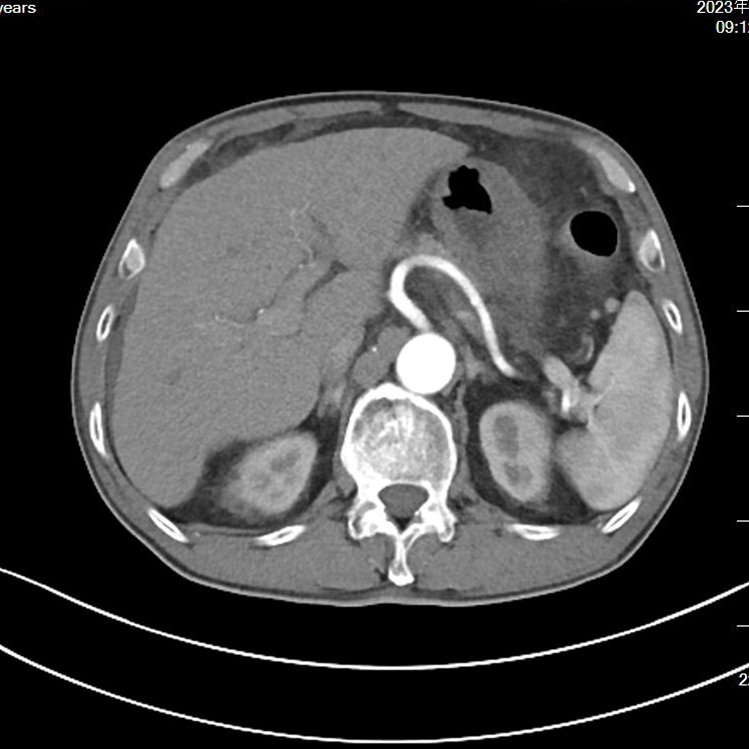

两程化疗后,瘤体未见明显退缩,距离根治机会相差甚远,老王多次表示要停止治疗返回老家等待生命终结,在陈主任和杨医生的一再劝慰、鼓励以及他儿女的坚定支持下,老王最终迎来了重生的曙光。第五次化疗后,老王的肿瘤终于出现了明显退缩,将原先侵犯的血管退出了瘤体,手术时机成熟。

▲新辅助治疗后